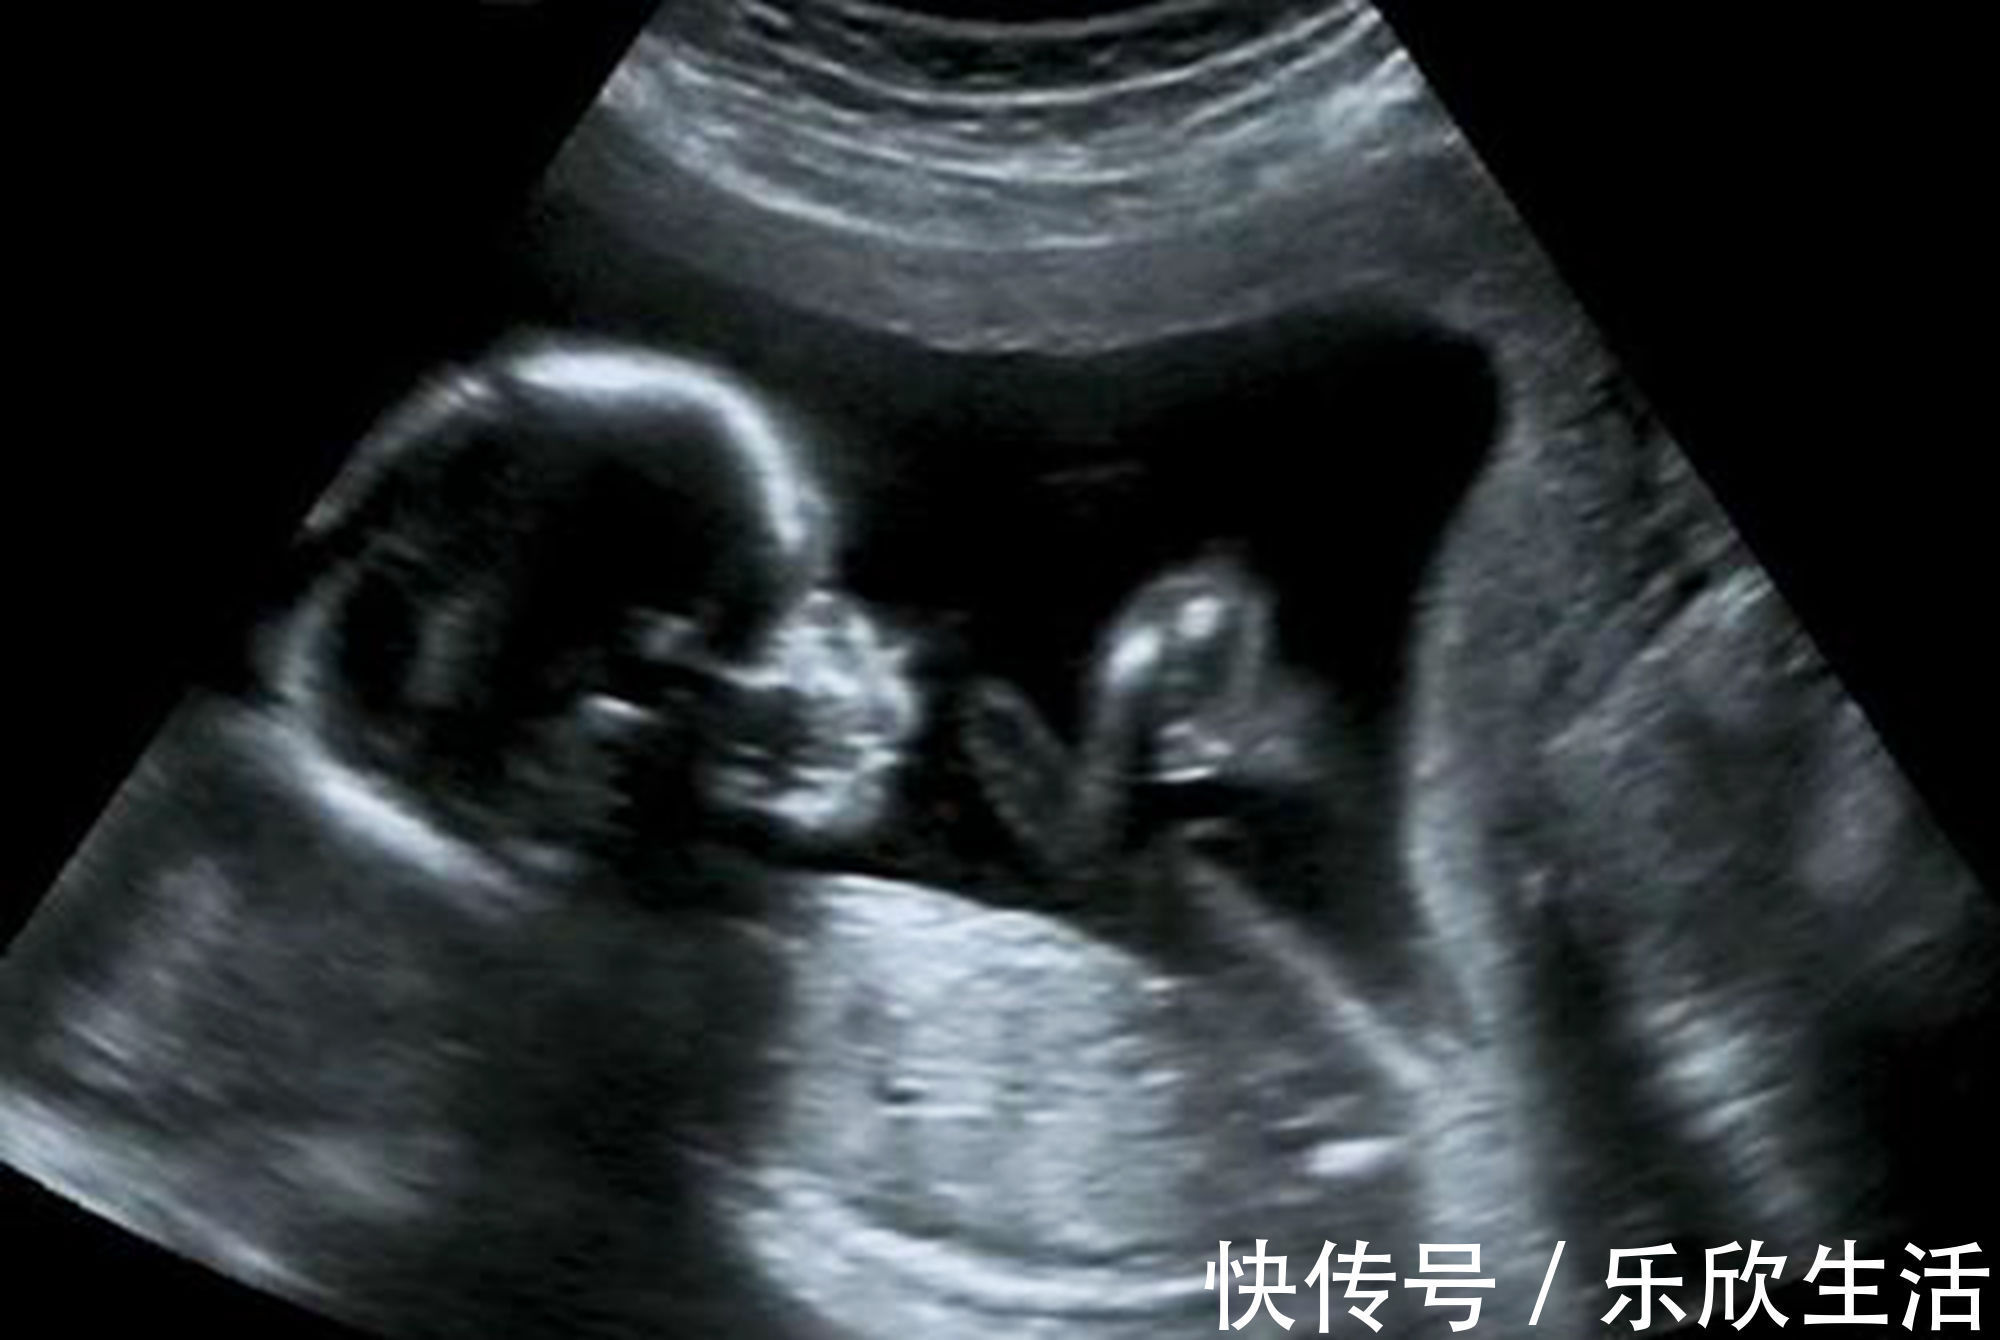

孕早期B超单上的四个指标,暗含了胎儿的“小秘密”,你看得懂吗?【 b超|孕早期B超单上的四个指标,暗含了胎儿的“小秘密”,你看得懂吗】孕囊,卵黄体,胎心,胎芽,被誉为判断胎儿的“四大指标”,孕早期这些数据,有着极其重要的临床意义。

在B超的图像中,孕囊仿佛一个黑色的小球,周围包裹着白色的外边。孕囊的变化很神奇,在孕妈妈怀孕5周时,医生就可以通过B超观察到它的影响了,随着胎宝宝的不断成长,到怀孕11周左右时,原始的孕囊却完全消失不见了,转换为胎盘,继续为胎儿提供营养。